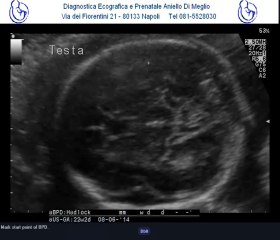

Difetto del setto atriale tipo ostium primum